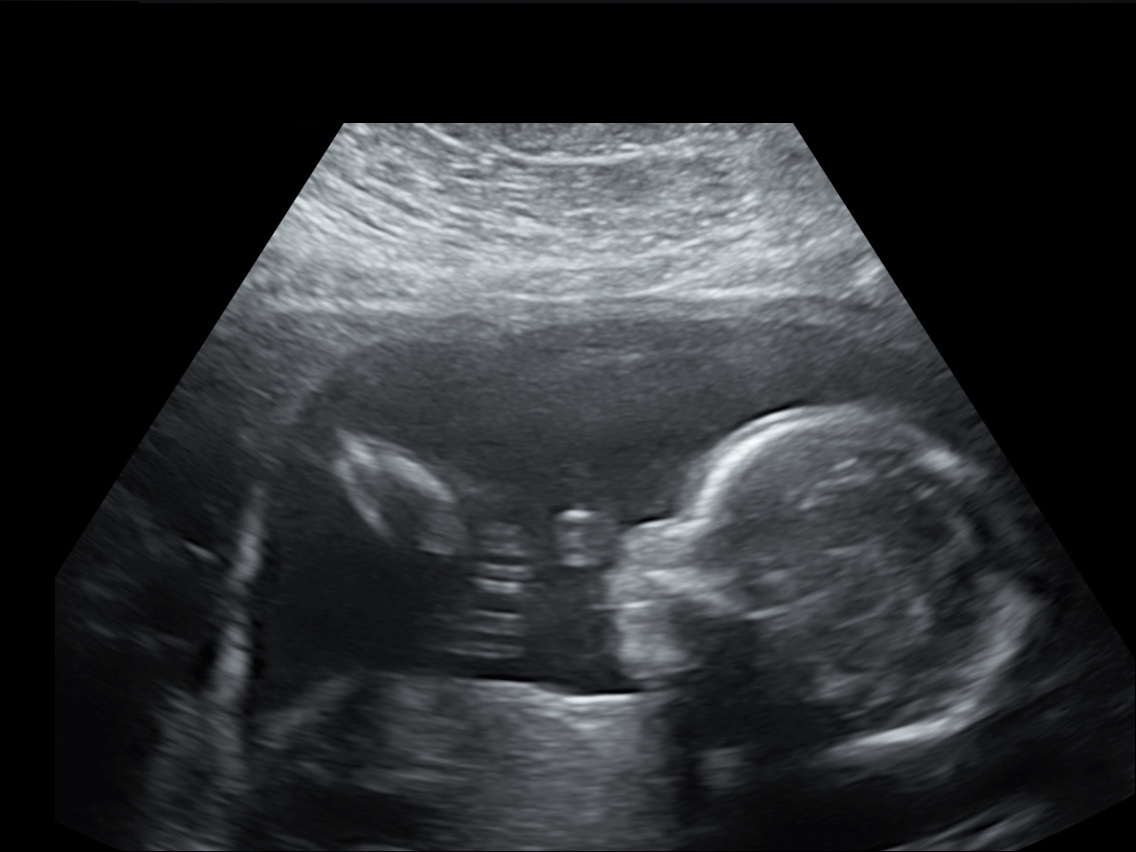

16 weken